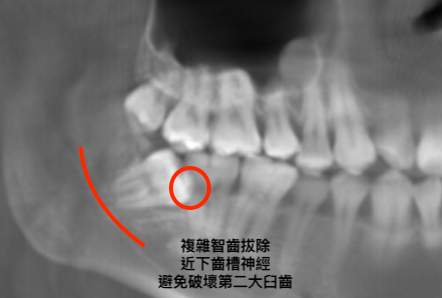

資料蒐集。全面檢查牙齒與骨頭,確認牙齒和顎骨神經位置(智齒)。評估身體狀況,並選擇適合的手術方式。